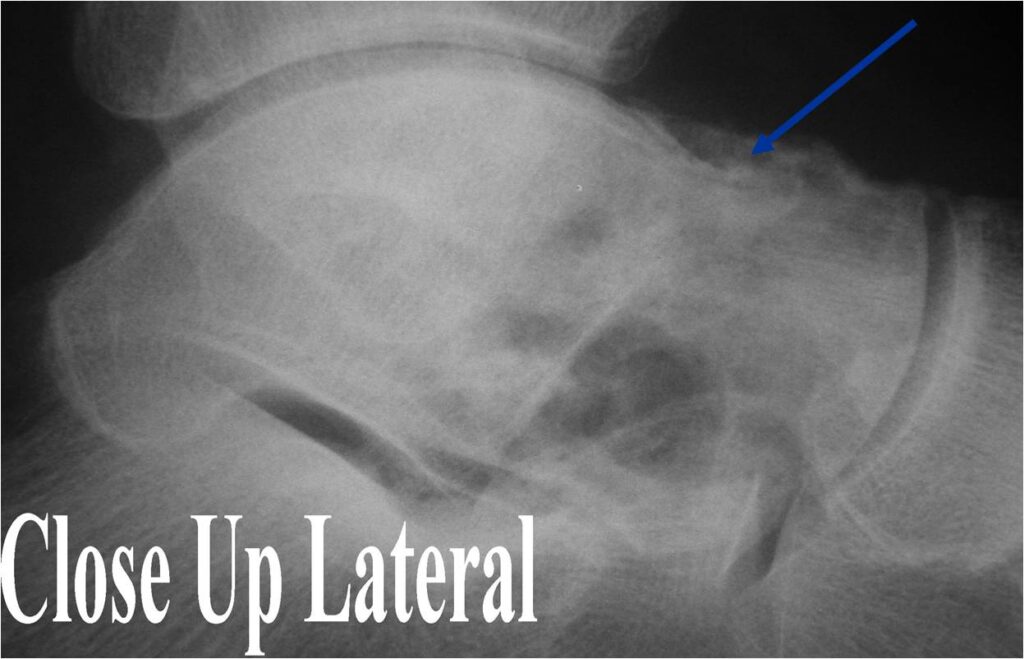

Radiographic Presentation

- Presents as a highly defined/well circumscribed geographic oval/round lytic defect

- Surrounded by rim of sclerotic bone

- Usually in epiphyseal region

- Lesion ranges from 3 cm to 6 cm diameter

- Usually radiolucent

- May have fine trabeculae and irregular calcifications

- Calcifications are often better detected with a CT scan but are not uniformly present

- Lesions may expand the bone and new periosteal bone may form

- Bony end plate, cortex, bone contour are unaffected

- (Plain x-ray appearance)

- Geographic lytic lesion IA/IB margin of sclerosis

- Usually Eccentric more often than Central in the bone

- Rarely expansile (rarely penetrates the cortex)

- Calcified chondroid matrix 30%-50% of cases

- Often better detected with a CT Scan

- Periosteal Reaction 30-50% of cases

- Usually occurs in Adjacent Diaphysis/Metaphysis since epiphysis is intraarticular and not surrounded by periosteum